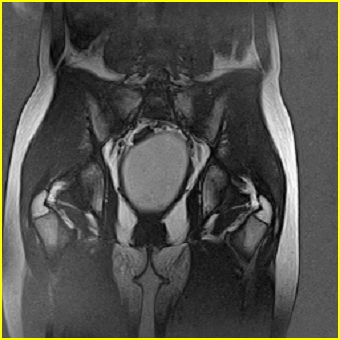

女、15岁、下腹疼痛2天,排尿困难1天。查体:处女膜闭锁,距处女膜约4至5cm处扪及一约5cm直径的圆形包块,张力较高,触痛明显、欠活动。b超提示子宫增大伴宫内增强回声团。

影像意见:子宫直肠陷凹积血。

更正影像意见:阴道积血。

处女膜闭锁,阴道积血

处女膜闭锁,阴道积血,子宫积血.

先天性处女膜闭锁,伴阴道积血,不除外先天性阴道粘液囊肿形成。

阴道积血,子宫积血.

子宫及阴道积血。

处女膜闭锁,伴子宫及阴道积血.